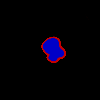

CCs exhibit lower underflow and overflow error.

We find that, compared to the baseline, CCs demonstrate more representative capacity, as evidenced by statistically significantly lower underflow and overflow across both datasets (Table 3). This representative capacity is clearly visualized in Figure 4. We also found that, for LIDC and FoggyBlob respectively, 42.96% and 50.16% of instances had (a trivial level of error) and 40.20% and 45.45% of instances had . In addition to these observations, we found that for individual instances experience less overflow than underflow () to a statistically significant degree ( for LIDC, for FoggyBlob) for LIDC and FoggyBlob respectively.

These results suggest that represents bounds on the range of singular annotations; that is, we would expect a singular annotation drawn by some annotator to fall within . Overall, the results suggest that a single CC annotation represents many uncertainty-relating structural properties across multiple singular annotations.